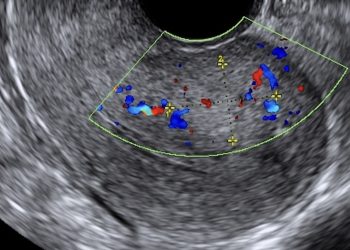

Cari soci, questo mese un nuovo video "How to do", dedicato allo studio ecografico della pelvi normale. Grazie a Carlotta...